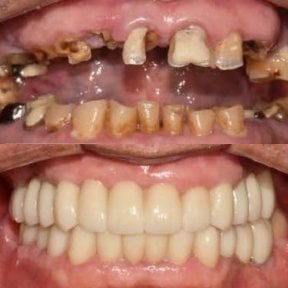

- Check reviews and patient photos. Look for real before-and-after cases and feedback from international patients.